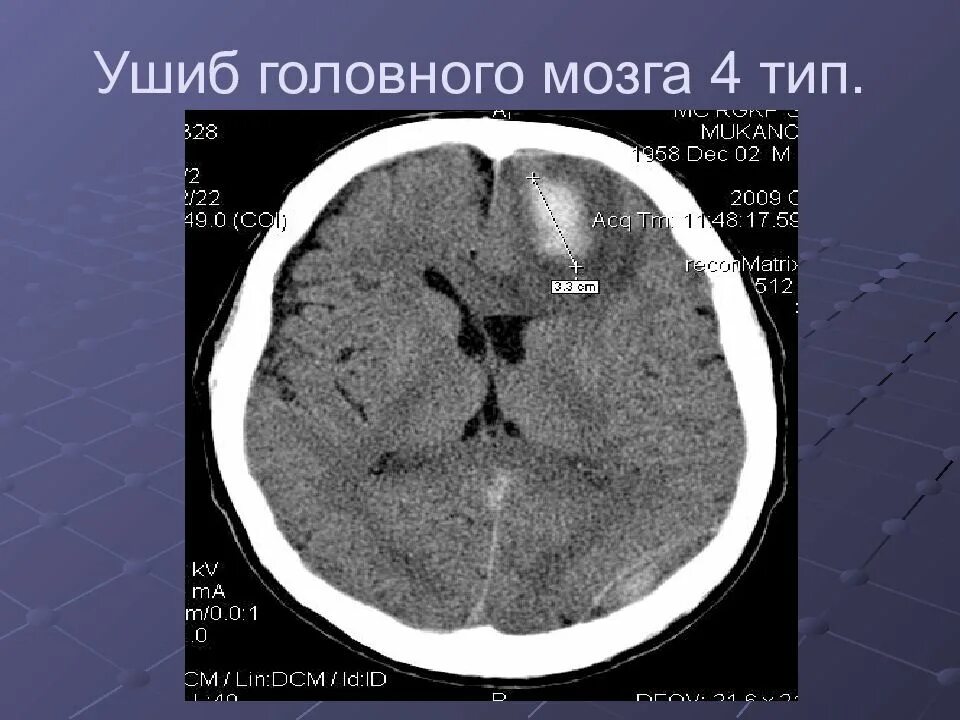

Что значит очаг в головном мозге